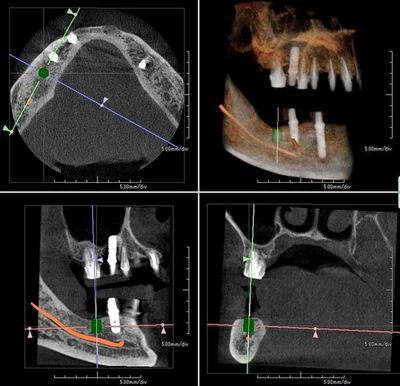

術前のCTシミュレーションです。

骨の横幅はたっぷりとありますが

下歯槽神経管(オレンジのライン)までの縦の幅が少ない状態です。

しかし、下顎において下歯槽神経管までの距離が少ない場合は

突き破らないように慎重にドリリングする必要があります。

それゆえに骨が少ない下の奥歯のインプラントオペが最も緊張します。

やはりインプラント治療には骨の状態のわかるCTが欠かせません。